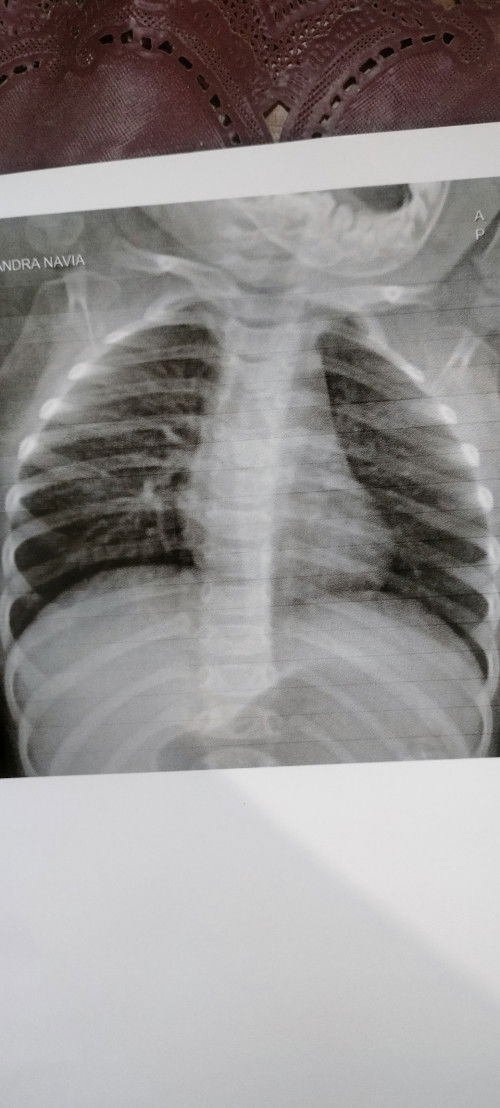

Anakku ini ada TB dan dinyatakan selesai pengobatan, nah waktu rongten anakku di diagnosa Broncopneumonia. Tapi waktu konsul k DSA, anakku ga di kasih obat apa2, katanya ga perlu di obati karna ga ada demam dan bapil. Apakah iya ga perlu penanganan lebih lanjut? Mungkin bunda2 ada yg berpengalaman #bantusharing #ingintahu